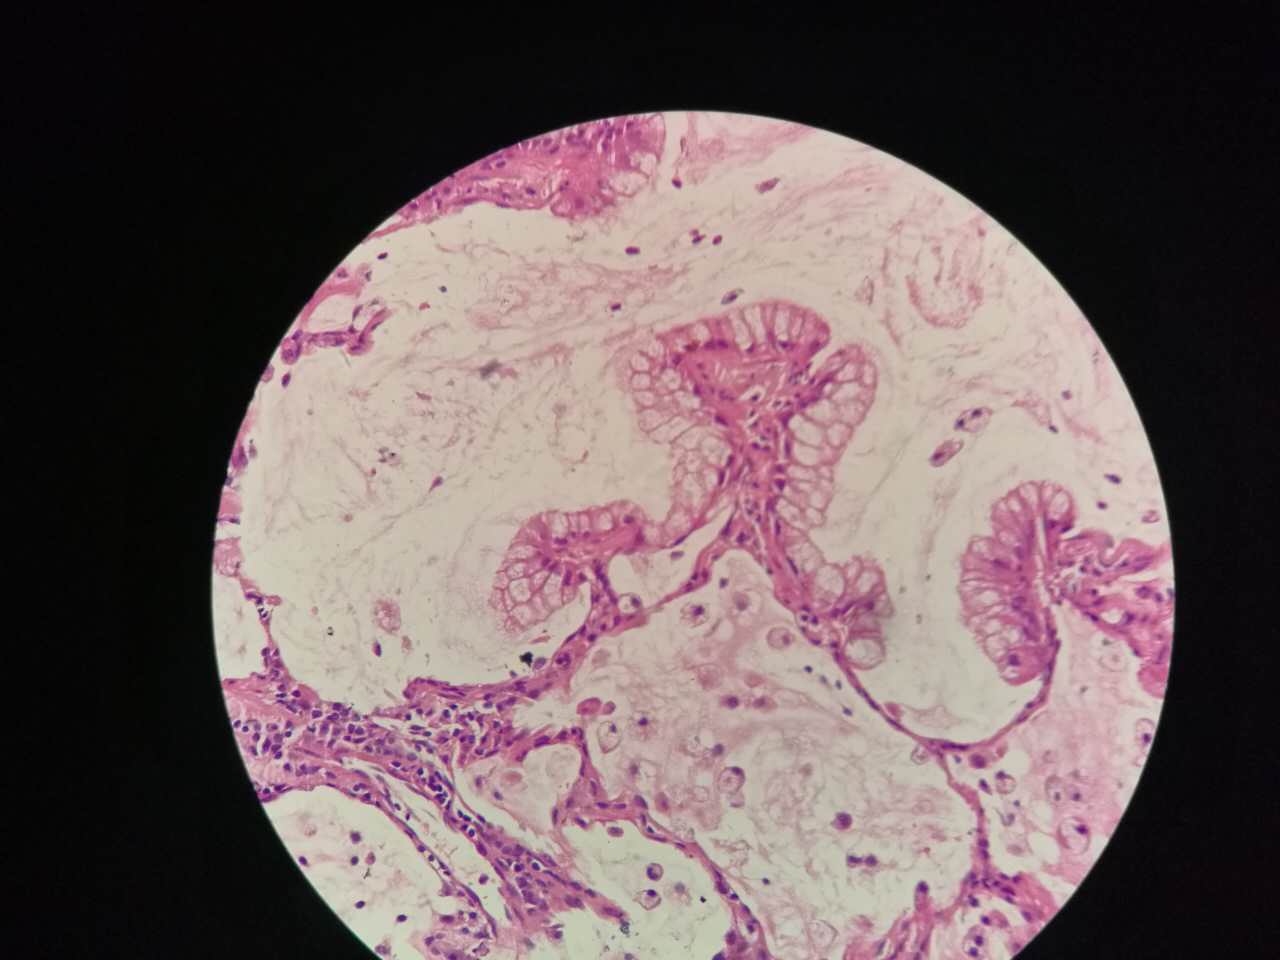

鳞癌生长,呈巢团状

巢团边界大多清楚

巢团可以很大,中央血供不足,就会坏死

中央红色的,有碎核

这个鳞癌不是早期

坏死也可以很大

较大的粉红区都是坏死,可以看出坏死是因为巢团大,中央坏死

左手边有一点鳞癌,右手边有正常肺泡组织,中间有坏死物,这是为什么呢?

坏死物质渗出。

并且可以有吞噬,坏死物里常有血液成分